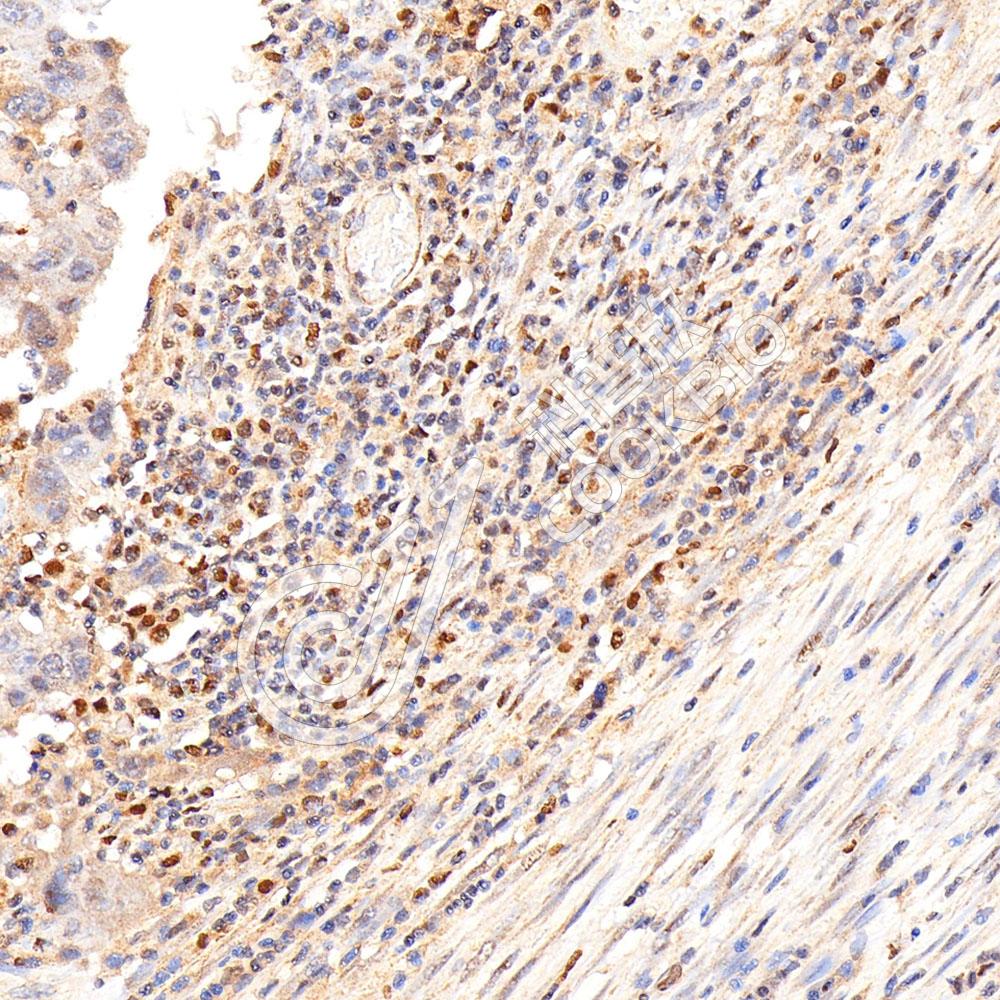

图像

WB检测Histone H3.

3蛋白(货号 K133078).

样品: 经RIPA裂解液(货号KSG2002)处理的蛋白质.

封闭: 3%脱脂牛奶(货号KSGC310001)溶于TBST溶液, 室温孵育1小时.

—抗: 1: 500稀释, 4℃ 孵育过夜.

二抗: HRP标记山羊抗兔IgG (H+L) (货号KB69909), 1: 5000稀释, 室温孵育1小时.